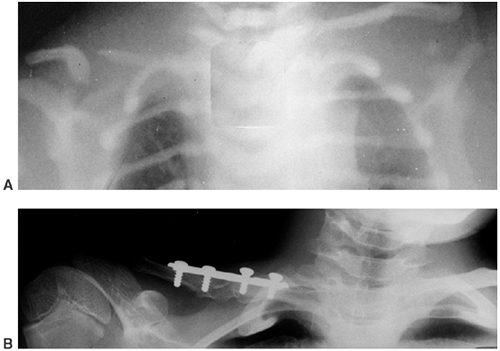

![]() |

Figure 10.6 An 8-and-a-half-year-old boy with idiopathic hemihypertrophy. A: Note the enlargement of the entire left lower extremity. The left upper extremity was enlarged as well. B: The lower extremity orthoroentgenogram demonstrates the leg-length discrepancy.